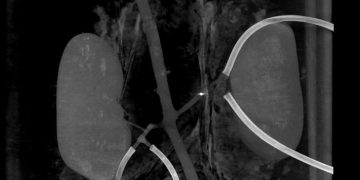

Миллиробот (яркая точка) пробивает себе путь через кровеносный сосуд

Ученые из Нидерландского университета Твенте и Медицинского центра Университета Радбауд провели успешное тестирование новой технологии по разрушению тромбов внутри кровеносных сосудов. Для этого они сконструировали специальных миниатюрных роботов, которые прокладывают себе путь через артерии. Механизмы получили название «миллироботы».

На самом деле это частный случай применения более обширной технологии, транспортной системы внутри кровеносных сосудов. Крошечные роботы напечатаны на 3D-принтере и имеют внутри постоянный магнит 1х1 мм. При воздействии внешнего магнита, который вращается в разных направлениях, робот также начинает двигаться, что и позволяет ему перемещаться внутри сосудов.

Такой робот может быть контейнером для доставки лекарственных препаратов в нужную часть организма. В варианте разрушителя тромбов он снабжен выступающими частями в форме штопора. Это позволяет роботу перемещаться против кровотока и «сверлить» сгустки крови, уничтожая их. Процедура сложная и деликатная, она требует точного управления внешним магнитом, чтобы провести миллиробота через сосуды, не повредив их.